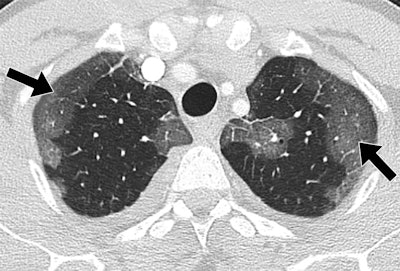

Patients hospitalized with MERS most commonly showed bilateral predominantly subpleural and basilar airspace changes, with extensive ground-glass opacities and less consolidation, concluded the study team from King Abdulaziz University Hospital in Jeddah. The subpleural and peribronchovascular nature of most of the abnormalities is suggestive of an organizing pneumonia pattern, they wrote.

The images showed that airspace opacities were more common than interstitial changes, according to the authors. Five patients had both ground-glass opacities and consolidation -- with ground-glass opacities being more extensive in all but one of those patients. One patient had only ground-glass opacities and another had isolated consolidation.

The radiologists found smooth septal thickening in three of the seven patients, and minimal peripheral reticulation, traction bronchiectasis, and perilobular opacities were found in just one patient. None of the patients had tree-in-bud pattern, cavitation, or intrathoracic lymph-node enlargement, the authors wrote.

The most common CT finding in hospitalized patients with MERS is bilateral predominantly subpleural and basilar airspace changes, with more extensive ground-glass opacities than consolidation, Ajlan and colleagues concluded.

"The predilection of the abnormalities to the subpleural and peribronchovascular regions is suggestive of an organizing pneumonia pattern," they wrote. "Recognizing this pattern in acutely ill patients living in or traveling from endemic areas may help in the early diagnosis of MERS-CoV infection."